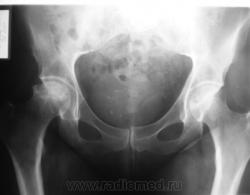

Левый для сравнения.

Асептический некроз головки правой бедренной кости, в стадии импрессионного перелома.

Очень похоже на Пертеса...

Согласен с наличием асептического некроза.

Асептический некроз. Не Пертеса, т.к. пациент явно старше 14 лет. У нас таких оперируют - эндопротез.

Да уж, господа, оставьте компанию Легг-Кальве-Пертеса в покое: этот Асептический некроз явно без них возник. Согласен с Иринкой в стадии.